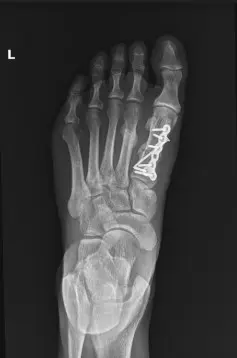

Follow-up X-rays demonstrated progressive healing of the fractures.

At three months, the patient demonstrated substantial improvement. She reported minimal pain, full weight-bearing without discomfort, and no longer required pain medications. Repeat X-rays confirmed excellent callus formation and maintained alignment of the metatarsals.

Postoperative internal fixation with plate and screws of a fracture of the first metatarsal.